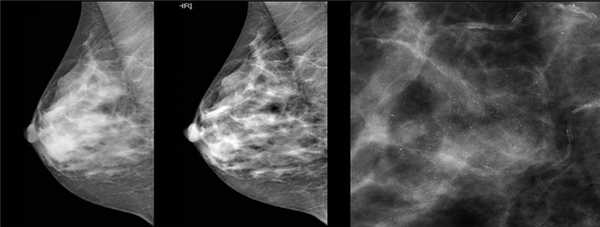

Для выявления злокачественных опухолей молочной железы существует определенный алгоритм диагностики, и его первичный элемент — маммографический скрининг. Чувствительность этого метода диагностики для опухолей от 2 мм до 5 мм составляет около 85%. Маммографическое исследование выполняют в двух проекциях.

Молодым женщинам с плотным строением молочной железы необходимо включение в программу наблюдения методов УЗИ и МРТ.